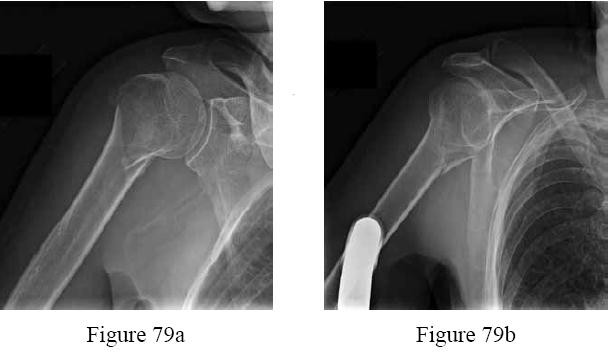

Figure 23Figure 23 is the radiograph of a 22-year-old woman who was involved in a motor vehicle collision. She reports isolated pain in her left shoulder. She is hemodynamically stable, respiring comfortably, and neurovascularly intact. Based on these findings, which of the following statements regarding treatment is most appropriate?